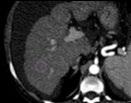

Figure 1: Workflow and results from the radiomic analysis of hepatocellular carcinoma nodules and peritumoural regions extracted from the waitlist placement CT scans of liver transplant candidates to predict disease recurrence.

Segmentation Feature Selection Modelling Arterial phase Portal venous phase Delayed phase = Nodule = +5 mm (PT_5) = +10 mm (PT_10) = +15 mm (PT_15) = Background Nodule AP-PVP PVP-DP AP-DP 0% 0% 20% 20% 40% 40% 60% 60% 80% 80% 100% InterVOI MRC >10% Interphase MRC >10% 100% PT_5 PT_10 PT_15 AUC (CI: 95%) P value Pseudo-R2 No. of RFs AP_Nodule 0.77 (0.65–0.90) 0.020 0.23–0.32 8 AP_PT_5 0.90 (0.83–0.97) <0.001 0.33–0.44 8 AP_PT_15 0.88 (0.76–1.00) <0.001 0.36–0.46 12 AP_Nodule_Norm 0.87 (0.75–0.98) <0.001 0.34–0.44 9 DP_Nodule_Norm 0.86 (0.77–0.95) <0.001 0.24–0.35 11 AP_PT_5_Norm 0.88 (0.80–0.97) <0.001 0.31–0.44 8 PVP_PT_10_Norm 0.88 (0.77–0.99) <0.001 0.35–0.45 8 PVP_PT_15_Norm 0.77 (0.65–0.89) 0.002 0.13–0.24 5

Redundancy: InterVOI: 14–26%

Interphase: 16–34%

Autocorrelation: 4%

AP: arterial phase; AUC: area under the curve; CI: confidence interval; DP: delayed phase; No: number; PVP: portal venous phase; RF: radiomic features.

■ = Arterial ■ = Delayed ■ = Portal

■ = Nodule ■ = PT_10 ■ = PT_15 ■ = PT_5

across arterial, venous, and delayed phases, with or without peritumoral region of 5, 10, and 15 mm. An area of ‘background’ liver parenchyma, distant from the lesions, was also segmented in each phase.

A total of 107 RFs, both directly extracted from segmentations, and normalised for the ‘background’ parenchyma, were obtained using PyRadiomics (Python Software Foundation, Beaverton, Oregon, USA). The normalisation was conducted by calculating the ratio between the RFs extracted from the VOI, and those extracted from the background segmentation. These features were then compared with each other for inter-VOIs and inter-phase relative change, while autocorrelation was assessed using Spearman’s rank correlation coefficient. RFs with relative change <10% and rank correlation coefficient >0.90 were considered non-informative. Informative RFs with different distribution in patients with and without posttransplant recurrence were selected to build multiple logistic regression models. Prediction of post-transplant recurrence was assessed by comparing the areas under the curve from receiver operating characteristic analysis and goodness-of-fit, expressed as the value range of Tjur’s, McFadden’s, and Nagelkerke’s R2 .

RESULTS

The CT scans of 53 patients were selected, resulting in a total of 1,032 segmentations from 86 nodules, with eight (15%) recurrence cases. When varying VOIs and phases, the proportion of noninformative RFs, indicating insignificant differences between the VOI and liver background, were 14–26% and 16–34%, respectively, while 4% of RFs showed autocorrelation >0.90.

The selected informative RFs allowed the building of eight predictive models with adequate performance and goodness-of-fit,

each comprising 5–12 RFs, with an area under the curve of 0.77–0.90 (p<0.02) and pseudo-R2 values of 0.13–0.46. A predominance of models derived from the arterial phase was observed, utilising the nodule with or without a 5 mm peritumoral region as the VOI, followed by the venous phase, including a 10–15 mm margin after normalisation (Figure 1).

CONCLUSION

Selection of optimal VOI and contrast phase combination is critical to maximise post-liver transplant HCC recurrence prediction using quantitative CT imaging. Specifically, segmenting the nodule, eventually including a 5 mm peritumoral region, during the arterial phase, or the nodule with a 10-15 mm margin during the venous phase after normalisation against the liver background, appeared to be the most promising strategy.●